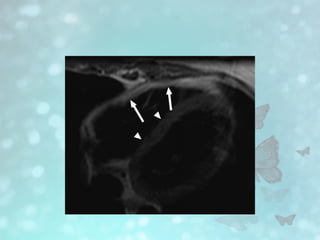

• MRI • CardiacMRI is the most sensitive diagnostic imaging modality. • Increased myocardial right ventricle (RV) signal suggesting fatty infiltration • Focal wall motion abnormalities • Increased right ventricular volumes with quantification, dilatation of the RV and right ventricular outflow tract (RVOT), thinning of the right ventricular wall. • Delayed myocardial enhancement suggesting fibro-fatty replacement

• #15 Black blood breath-hold T1-weighted MR image shows diffuse fatty infiltration of right ventricle. Note increased signal intensity from fat in free wall of right ventricle (arrows), compared with intermediate signal intensity from septum and left ventricular wall (arrowheads)